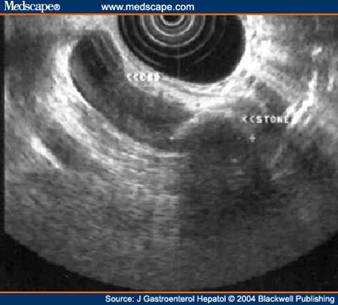

Ultrasonografia endoscopica consiste nell'introduzione di una sonda ad ultrasuoni ad alta frequenza ( 7.5-12 Mghz) nel sistema digerente fino al duodeno sotto guida endoscopica. Un pallone riempito d'acqua è usato come finestra acustica.La sensibilità e la specificità di questa tecnica sono riportate in un range che va dall'85 sino al 100%.Questa tecnica garantisce risultali significativamente migliori rispetto all'approccio trans addominale ma risulta penalizzata sotto molteplici aspetti tra cui ricordiamo la notevole invasività , il consistente aumento dei costi e la necessità di disporre di personale altamente specializzato. 22

Fig 3 ecoendoscopia. Presenza di voluminoso calcolo nel coledoco